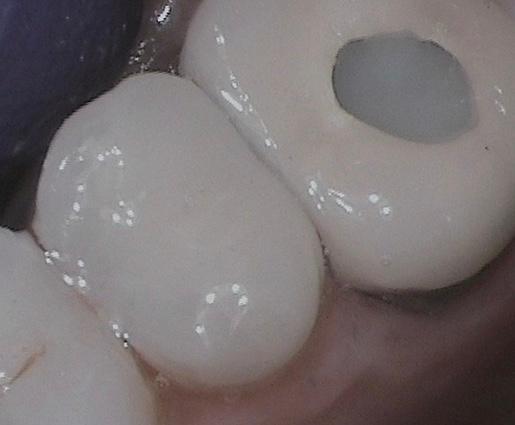

Chipped old filling with recurrent decay was restored with Porcelain Inlay in less than 2 hours. No second visit!